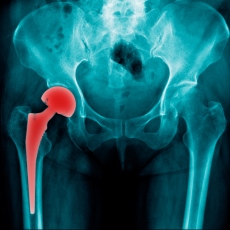

Hip replacement is surgery for people with severe hip damage. The most common cause of damage is osteoarthritis. Osteoarthritis causes pain, swelling, and reduced motion in your joints. It can interfere with your daily activities. If other treatments such as physical therapy, pain medicines, and exercise haven't helped, hip replacement surgery might be an option for you.

During a hip replacement operation, the surgeon removes damaged cartilage and bone from your hip joint and replaces them with new, man-made parts.